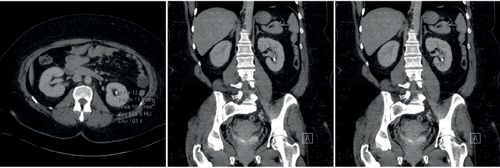

Figure 1a. 650HU, lower pole stone with a wide (11mm) and short (11mm) infundibulum.

Figure 1b. 635HU, lower pole stone with a narrow (1.5mm) and long (21mm) infundibulum.

The maximum SSD varies according to the lithotripter in use and its specific focal length; but studies generally point to an SSD<10cm as appropriate. Although ESWL can treat (i.e. fragment) stones in all calyces, those within the lower pole have the lowest rate of clearance (25%). The intra-renal anatomy affects this further, with a wide (>5mm), short (<10mm) infundibulum, with a shallow infundibulo-pelvic angle (>70o) allowing better clearance of fragments than if the stone is at the end of a tight, long infundibulum.

Hounsfield unit density can be used as a guide to the stone’s ‘hardness’, with various studies giving different cut-off values for predicting success. Hard stones (calcium oxalate monohydrate, or the ‘Brushite’ form of calcium phosphate stones) fragment less readily and therefore are more likely to cause obstruction on travel or indeed may not fragment at all. Ouzaid et al. evaluated the outcome four weeks after ESWL by non-contrast computed tomography (NCCT) and found that patients whose stones had a Hounsfield unit density <970 had a stone-free rate (including “clinically insignificant residual fragments ≤4mm”) of 96%, but this was just 38% if the stones HU density was ≥970HU (P<0.001) [15]. Furthermore, various parameters can be combined to give even more precise prediction of stone-free rates: using a combination of stone density <600HU, skin-to-stone distance <12cm and stone volume, Tran et al. demonstrated a likelihood of being stone free increased from 21.4% (if all parameters were unfavourable) to 96.1% if all were favourable [16].